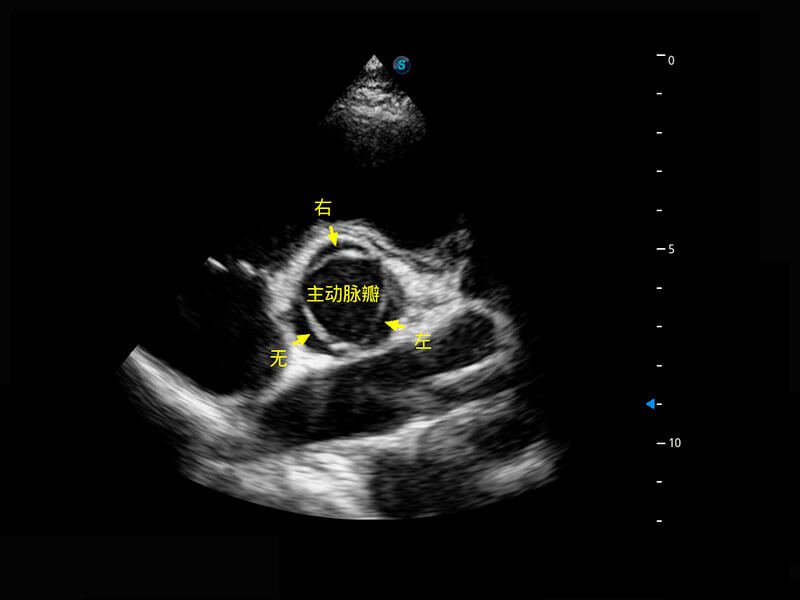

P60搭载一系列胎儿心脏成像技术,实现精细的胎儿心脏评估。

四腔切面

四腔心血流

右室双出口